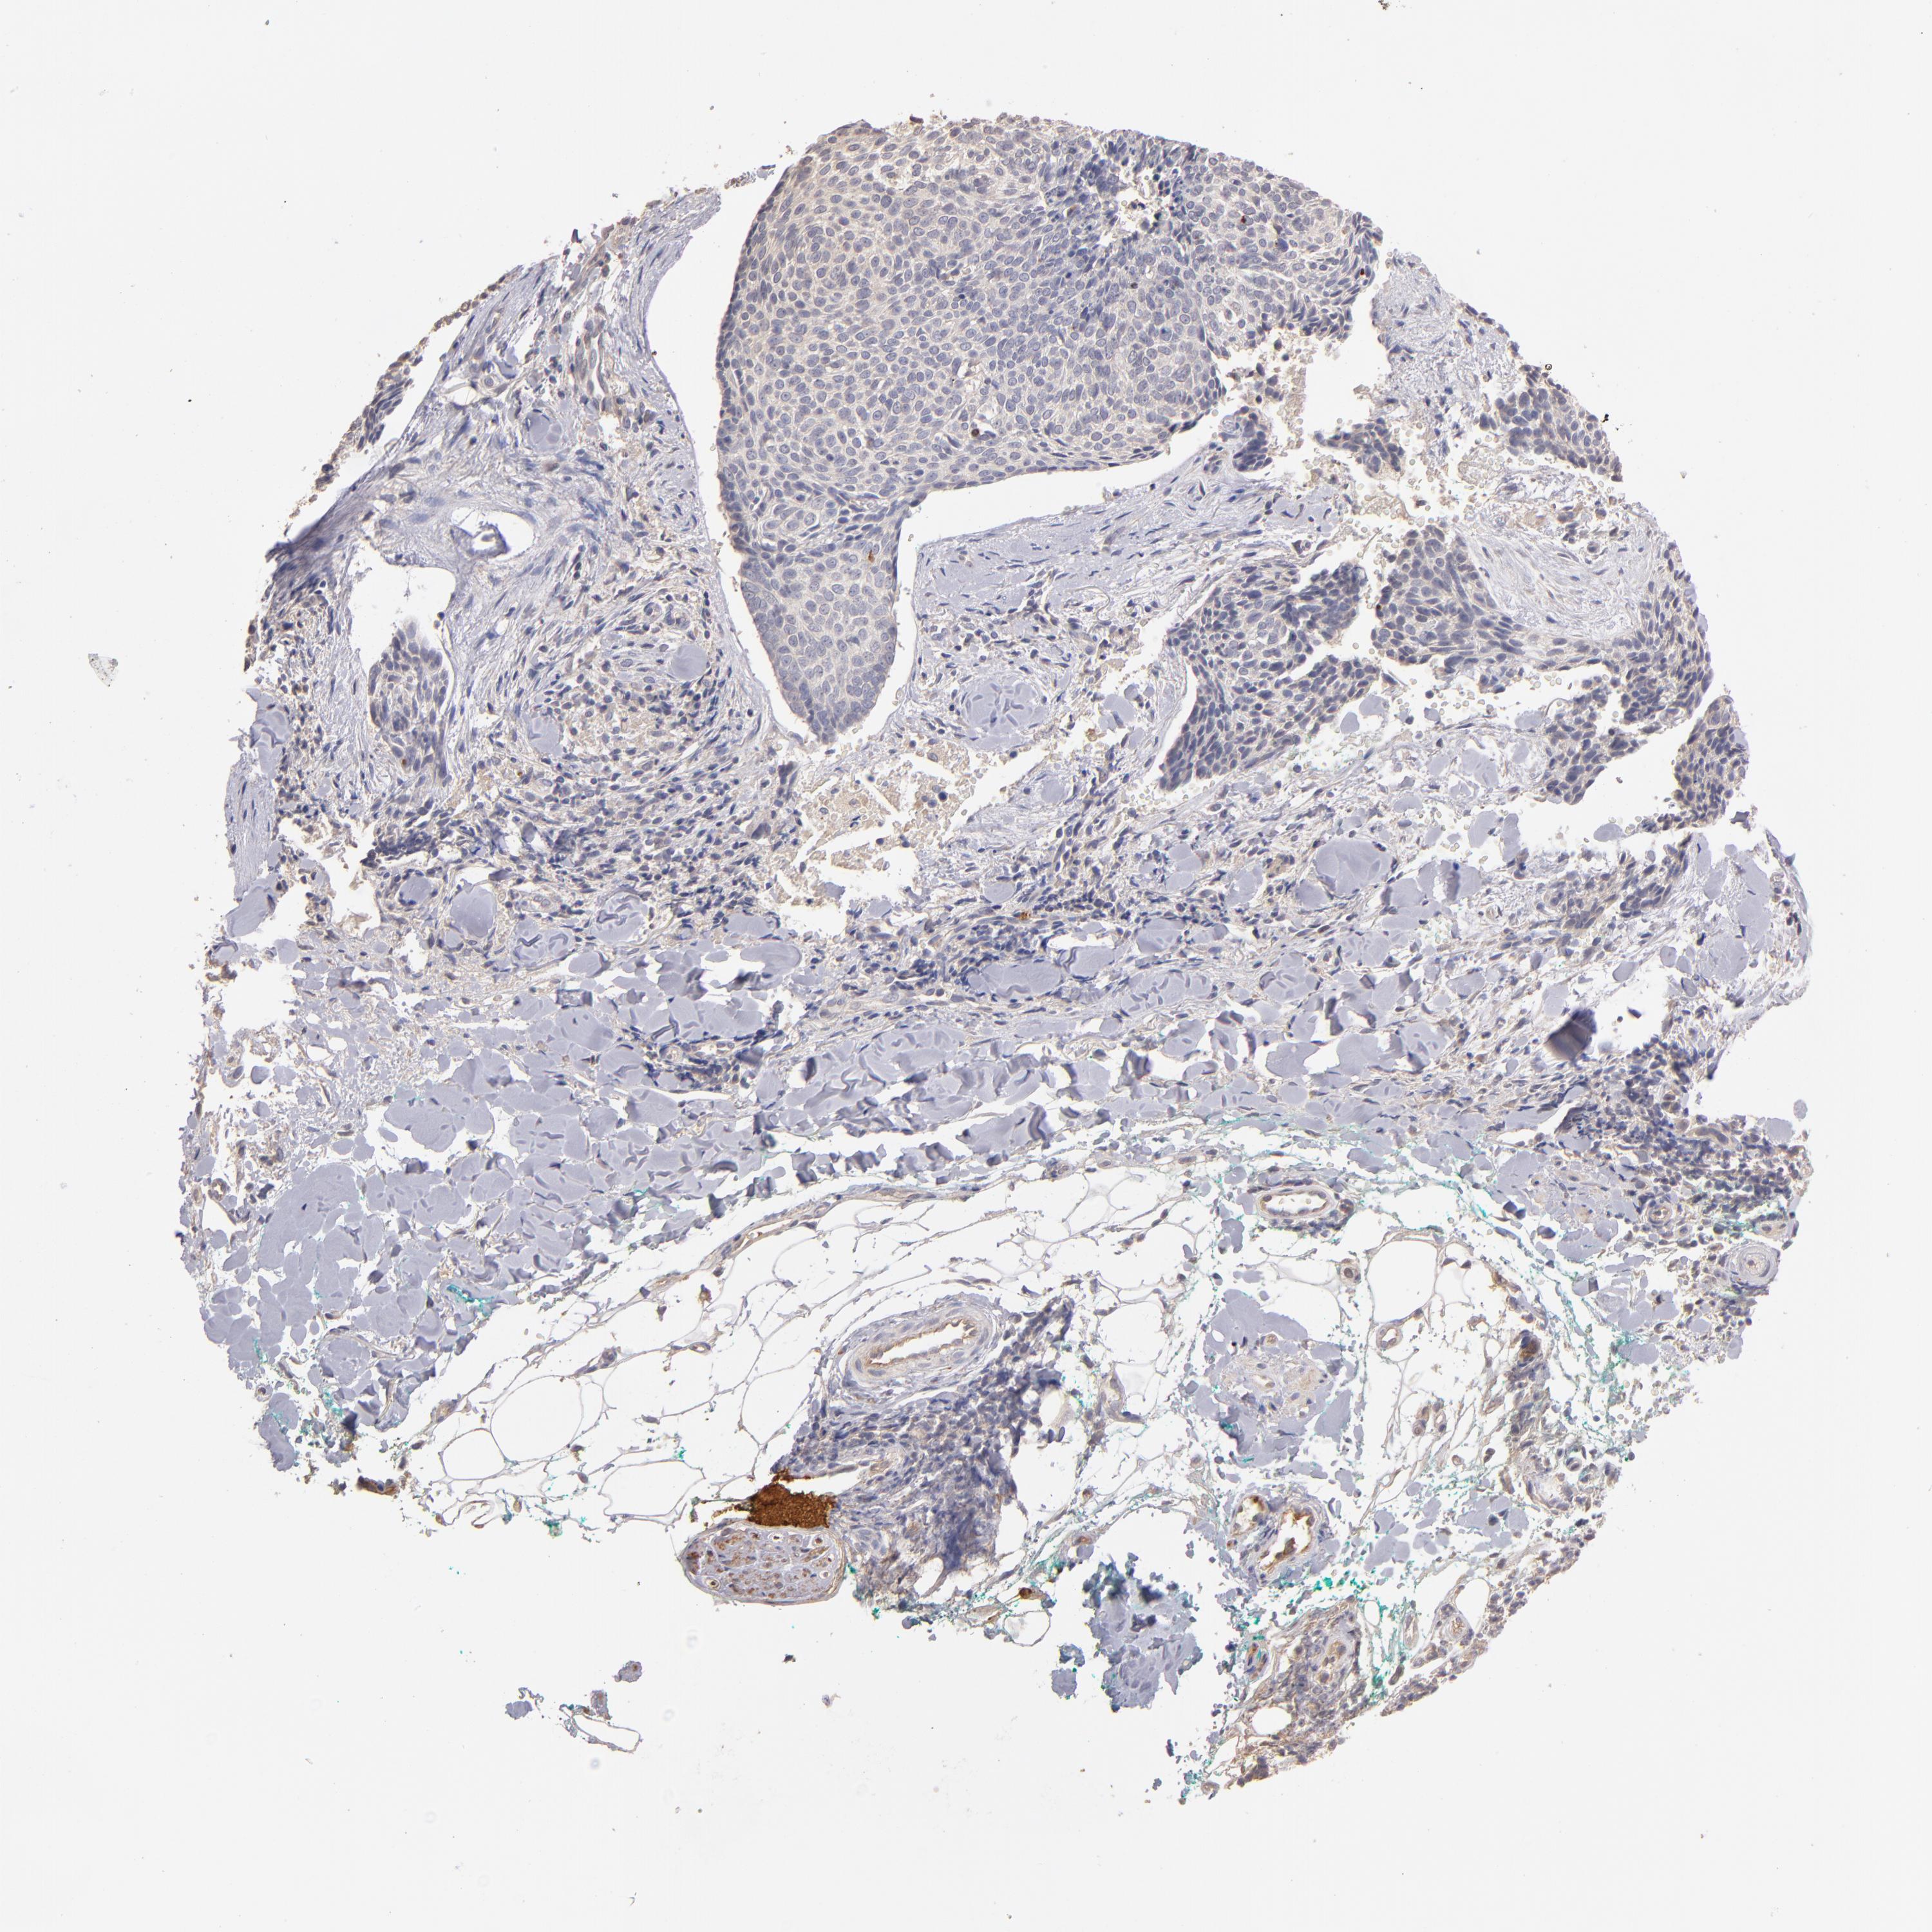

SKIN CANCER - Protein expressioni

A mouse-over function shows sample information and annotation data. Click on an image to view it in a full screen mode. Samples can be filtered based on level of antibody staining by selecting one or several of the following categories: high, medium, low and not detected. The assay and annotation is described here.

Antibody staining in the annotated cell types in the current human tissue is reported as not detected, low, medium, or high, based on conventional immunohistochemistry profiling in selected tissues. This score is based on the combination of the staining intensity and fraction of stained cells.

Each image is clickable and will lead to virtual microscopy that enables deeper exploration of all samples and also displays staining intensity scores, fraction scores and subcellular localization as well as patient and tissue information for each sample.

Antibody HPA003011

Basal cell carcinoma